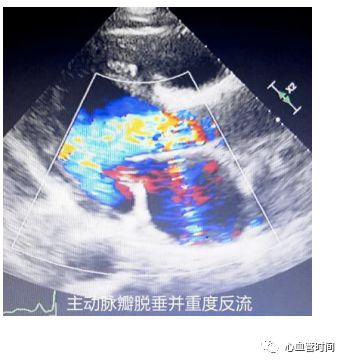

主动脉瓣观察有无钙化、畸形、狭窄、反流、脱垂。当存在二叶瓣畸形时,可见两个瓣叶

闭合点不居中、偏向一侧,瓣叶大小不同;狭窄时可见瓣叶

活动度减小,开放受限。且风湿性二尖瓣狭窄往往会累及主动脉瓣,则需注意观察是否合并主动脉瓣病变;脱垂时可见

一侧瓣叶于舒张期

脱向左室侧,往往存在大量反流。

主动脉瓣观察有无钙化、畸形、狭窄、反流、脱垂。当存在二叶瓣畸形时,可见两个瓣叶

闭合点不居中、偏向一侧,瓣叶大小不同;狭窄时可见瓣叶

活动度减小,开放受限。且风湿性二尖瓣狭窄往往会累及主动脉瓣,则需注意观察是否合并主动脉瓣病变;脱垂时可见

一侧瓣叶于舒张期

脱向左室侧,往往存在大量反流。